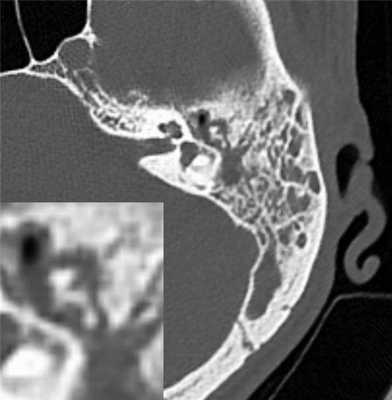

На серии снимков аксиальной компьютерной томографии с последующей трехмерной реконструкцией визуализируются типичные признаки среднего отита: тотальное снижение пневматизации ячеек сосцевидного отростка, антрума и барабанной полости за счет патологического содержимого мягкотканной плотности, без явных признаков некроза височной кости: деструктивных изменений ячеистой структуры сосцевидного отростка, наличия секвестров. Отмечаются также и определенные изменения, нехарактерные для типичной клинической картины среднего отита, но являющиеся сугубо специфическими: наковальня (тело) и молоточек (головка) представляются выраженно кариозно измененными (рис. 2).

Рис. 2. Компьютерная томография височных костей (AD).

Таким образом, представлено редкое наблюдение туберкулезного среднего отита на фоне ВИЧ-инфекции, которое демонстрирует агрессивный характер течения заболевания с прогрессирующими органическими изменениями и характерной отоэндоскопической картиной: на компьютерной томограмме присутствуют как типичные признаки отита, так и изменения, характерные для кариозного процесса, обусловленного специфической инфекцией.